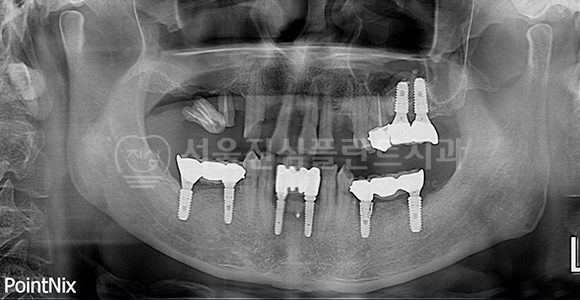

임플란트 재수술 + 상악동 거상술

BEFORE

AFTER

상악동 거상술 측방접근법 + 기존 임플란트 제거 후 재수술